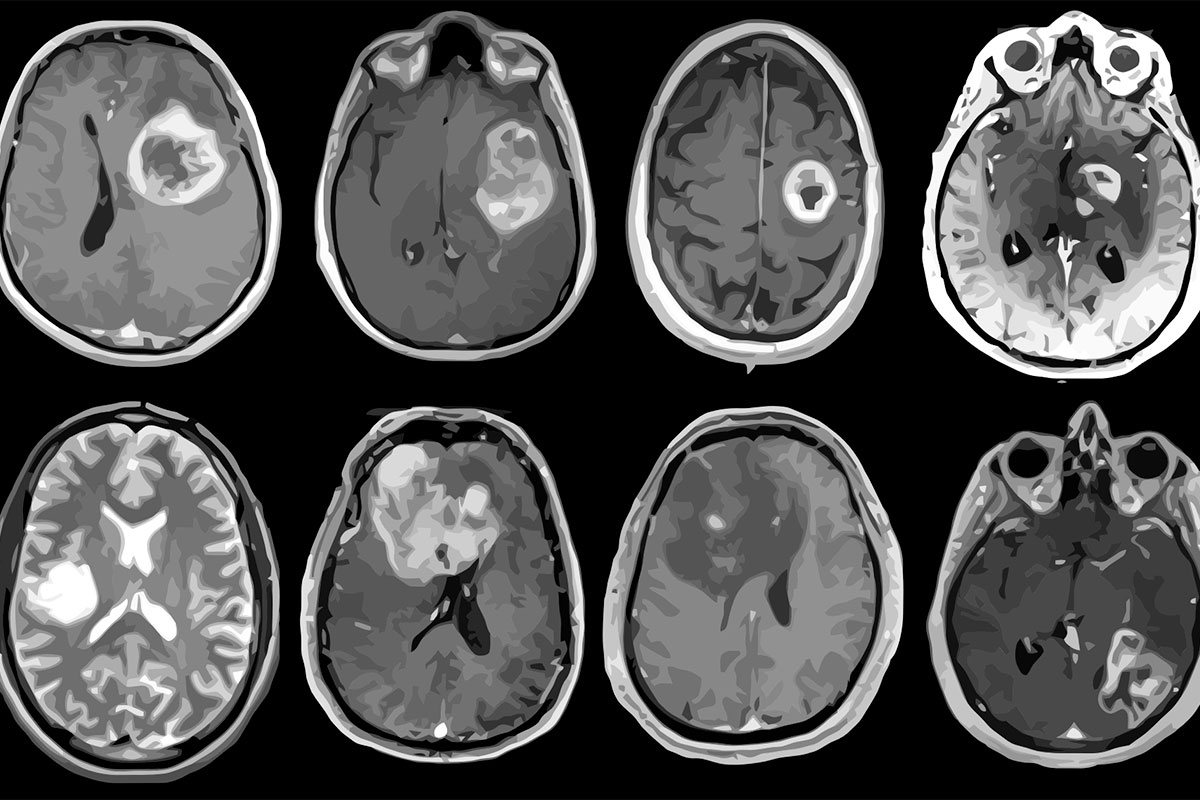

NeuronB takes two MRI scans with different markers (FLAIR and T1Gd), runs them through a deep learning model to segment the tumor, and returns a 3D visualization — all within seconds. The result is an easy-to-understand, 3-dimensional model of the tumor in the brain space, giving a clearer idea of where the tumor exists that might be difficult to see through a series of 2D MRI slices.

We trained a 2D UNet model off of the NIH's BraTS-TCGA-LGG dataset, slicing each of the 3D MRI's into 2D tensors based off of 2 different tumor markers, and then feeding it into a training cycle over 15 epochs.

IMPORTANT STATISTICS (SEE IMAGES ATTACHED) Final Val Loss = 0.0098 (lower is better) Final Dice Score = 0.9421 (1 is perfect)